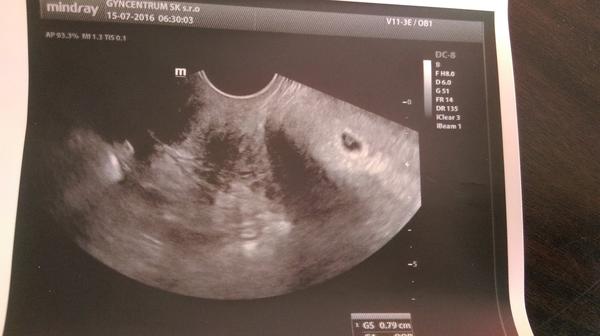

Prikladam ti foto prvá je 4+6 tt a druhá je 5+2 tt ,tam už vidieť zltkovy vak aj embryjko zatim bez srdiečka uvidím na ďalšej kontrole ..😍😍😍a posledná foto je len tak aby si sa vedela orientovať 😘😎